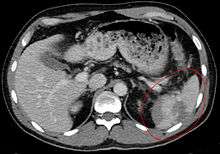

Splenic rupture is usually evaluated by FAST ultrasound of the abdomen.[3] Generally this is not specific to splenic injury; however, it is useful to determine the presence of free floating blood in the peritoneum.[3] A diagnostic peritoneal lavage, while not ideal, may be used to evaluate the presence of internal bleeding a person who is hemodynamically unstable.[4] The FAST exam typically serves to evaluate the need to perform a CT.[4] Computed tomography with IV contrast is the preferred imaging study as it can provide high quality images of the full peritoneal cavity.[3]